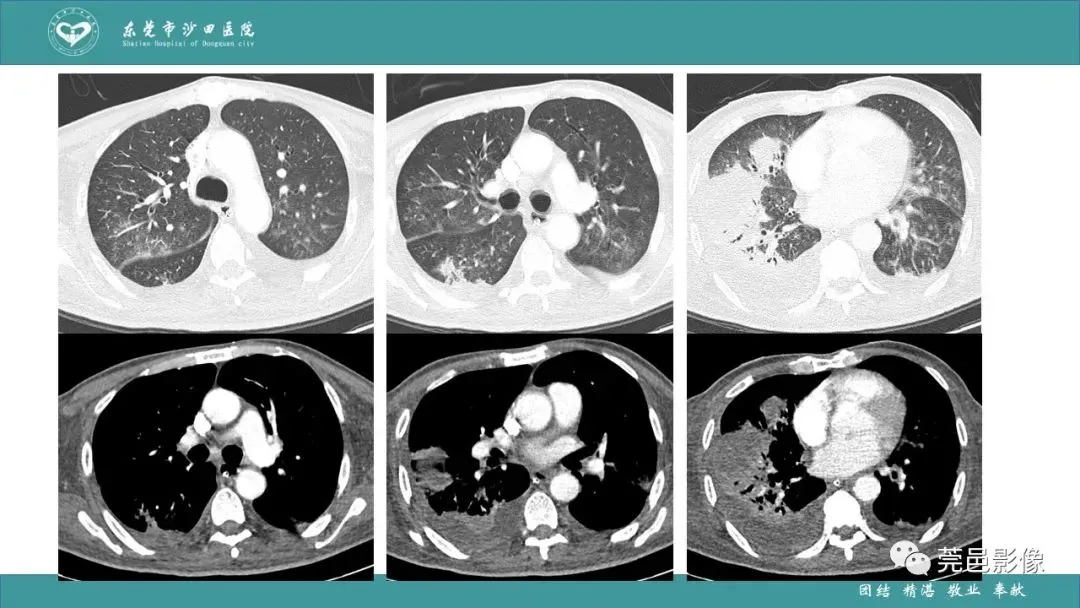

>课件 | 肺炎克雷伯杆菌肺炎影像学诊断与鉴别诊断

课件 | 肺炎克雷伯杆菌肺炎影像学诊断与鉴别诊断